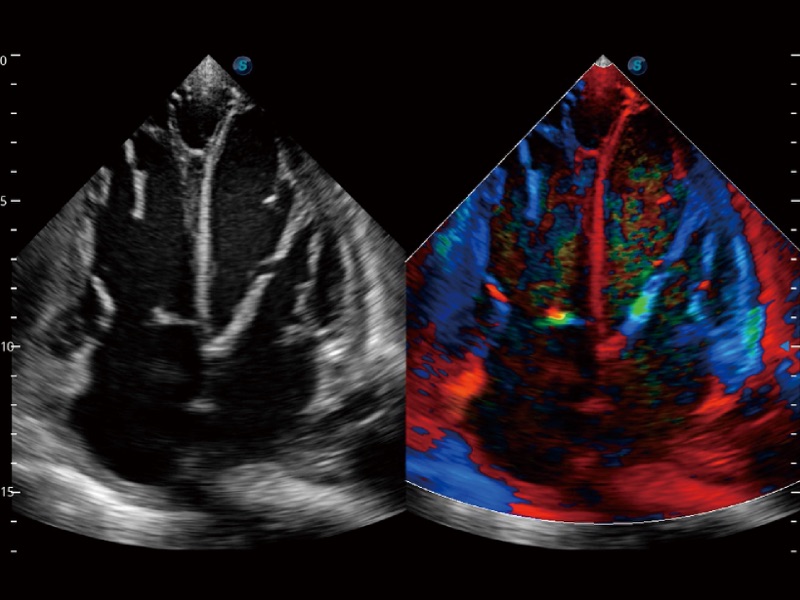

高分辨率血流成像技术提高了对低速血流信号的检测能力。在提高空间分辨率的同时,也克服了血流外溢现象,为用户提供更加真实的血流动力学信息。